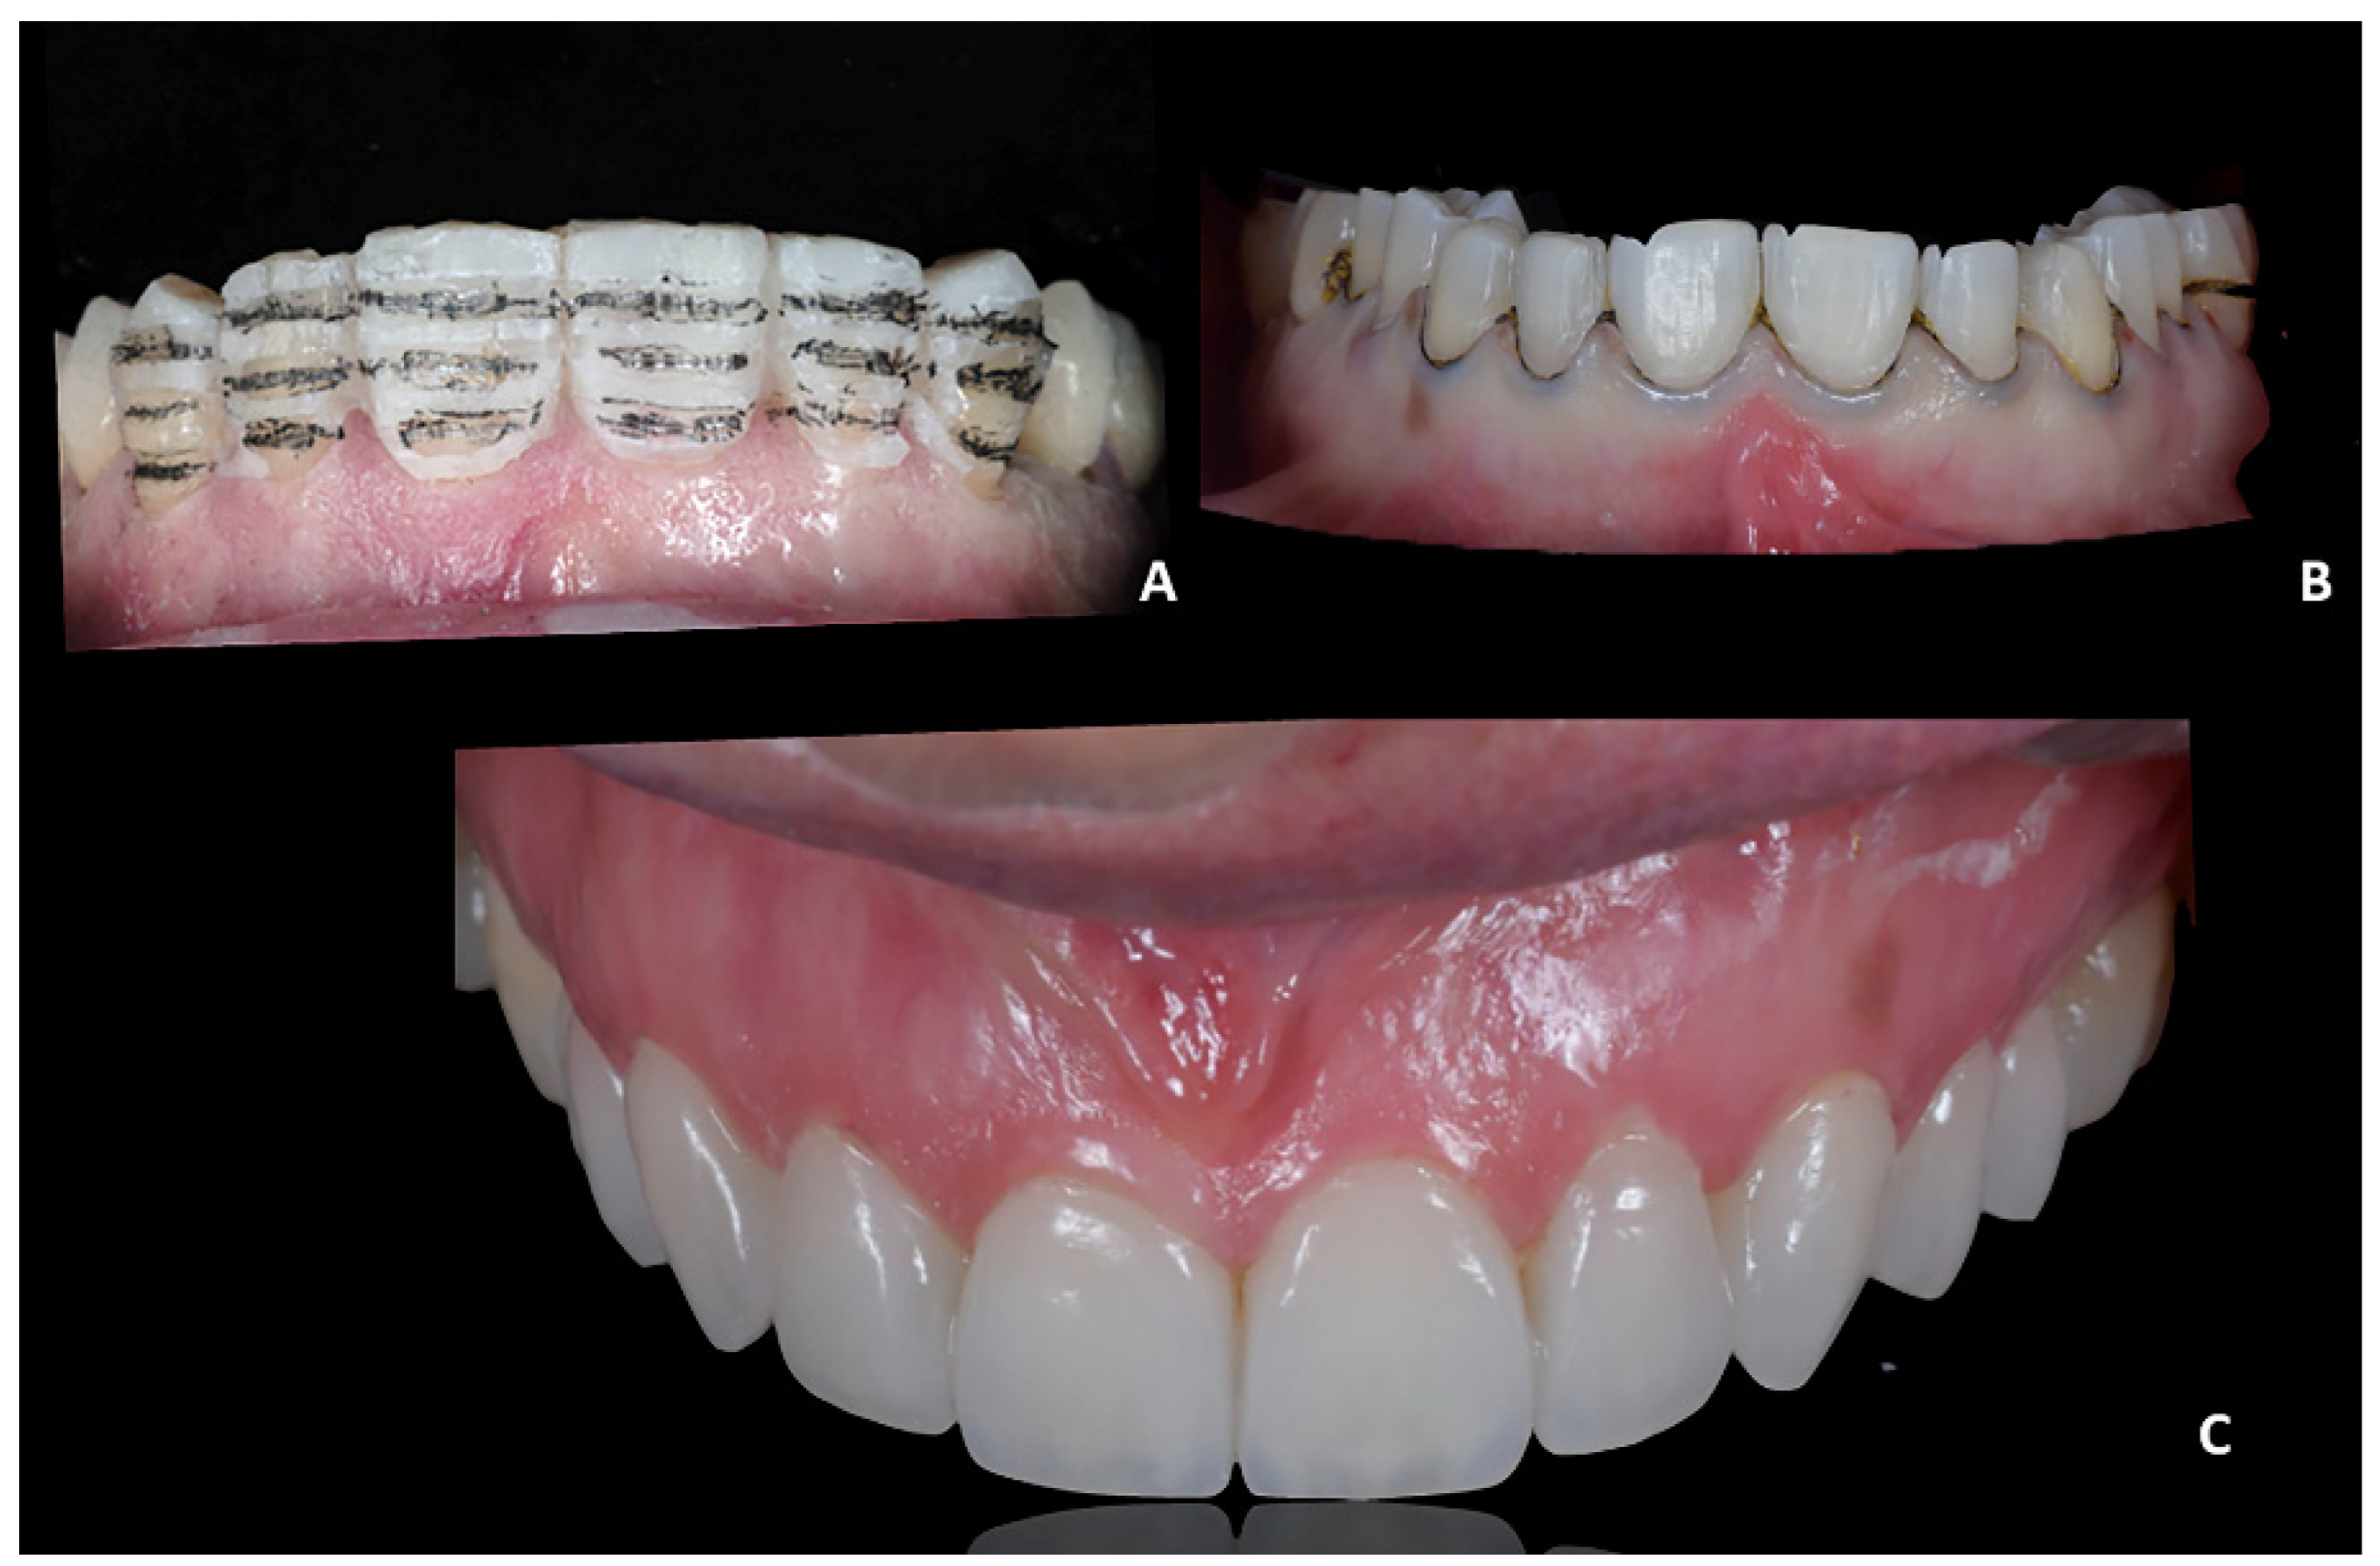

5.

Prosthetic finalization. After orthodontic treatment, posterior rehabilitation was completed by replacing the temporary crowns with monolithic zirconia crowns screwed on implants (Figure 19A). In the same appointment, provisional crowns were applied in the upper anterior segment from 1.3 to 23 and kept for one month (Figure 19B). After the final aesthetic and functional analysis wards, the case was finalized by replicating the information and functional characteristics of the provisional crowns in the final definitive prosthesis (Figure 20). The upper fixed prosthesis was zirconia-ceramic, stratified in the vestibular (not functional) area.

Figure 20. Case 3. The case was finalized by replicating the information functional characteristics of the provisional crowns in the final definitive prosthesis. (A) Intra-oral frontal view; (B) occlusal upper view; (C) occlusal lower view.